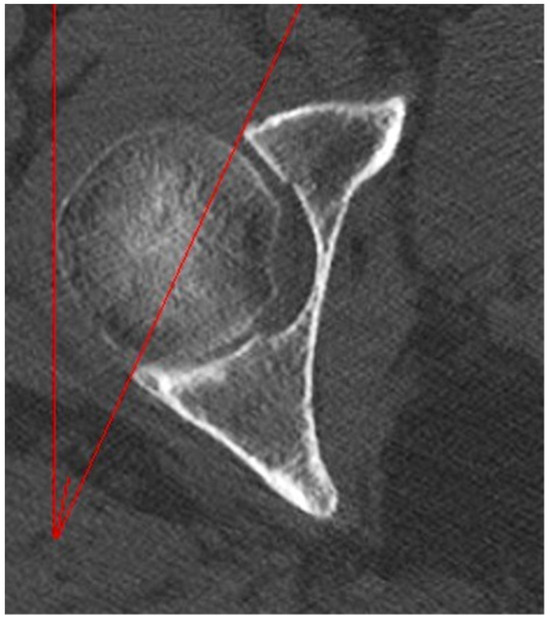

2.2. Measurements

| Femoral Version | 16.00° ± 4.53° (15.22°–16.78°) | 13.16° ± 4.37° (12.31°–14.01°) | 0.0001 |